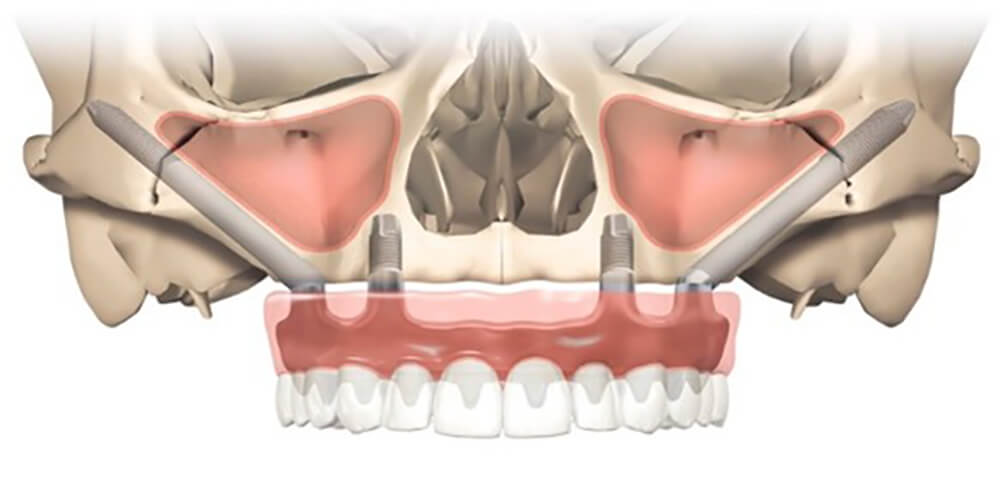

All-on-4 全口重建術式原理是植入 4 顆特殊設計的植體,藉由造橋力學原理,讓力量平均分散支撐整排牙齒。若患者骨質無法達到 All-on-4 全口重建傾斜植體的條件,Zygoma implant 顴骨植體就是最後秘密武器,顴骨是顏面主要支架,骨質密度高且強壯,不易隨著時間流失,足以提供植體良好穩定性,讓骨質不佳的患者也有接受 All-on-4 全口重建治療的機會。

這次All-on-4 全口重建案例盤太太,經醫師評估後即使用 2 根顴骨植體來確保全口重建假牙的穩固。(延伸閱讀:【顴骨植體】骨頭不好無法做All-on-4全口重建? Zygoma implant 顴骨植體有解!)